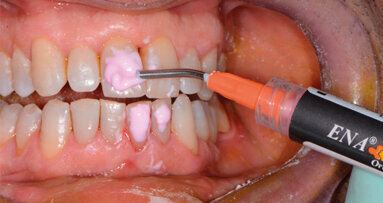

Il presente lavoro descrive la procedura con laser neodimio Nd:YAG 1064 nm per intervento di perimplantite.

Paziente di sesso femminile di anni 27 con anamnesi generale negativa e senza storia di malattia parodontale, si presenta in prima visita lamentando ...